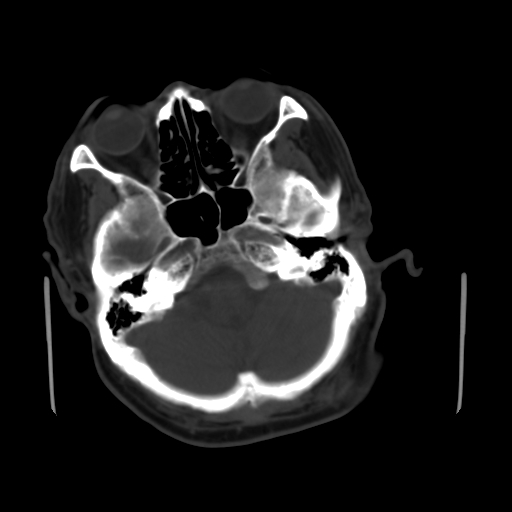

标题: CT25147:男,62岁,右侧肢体活动障碍不灵活三天。 [打印本页]

男,62岁,右侧肢体活动障碍不灵活三天,左侧头皮肿物十余年(ct值8hu)。

多发腔梗!皮下脂肪瘤!

1)多发性腔隙性脑梗塞。2)脑白质病。3)脑萎缩。4)左侧枕顶部头皮下皮样囊肿,不排除脂肪瘤。